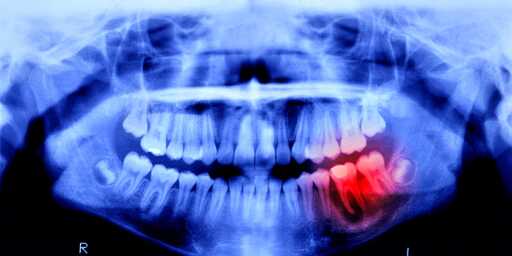

Gum disease could lead to tooth loss but the primary way people lose them is through infections due to cavities. The infection weakens the tooth and the jawbone it’s rooted in as well as can lead to loss of the root nerve. At a certain point the tooth is too loose or weak and has to be removed to prevent further infection and/or to treat the existing infection.